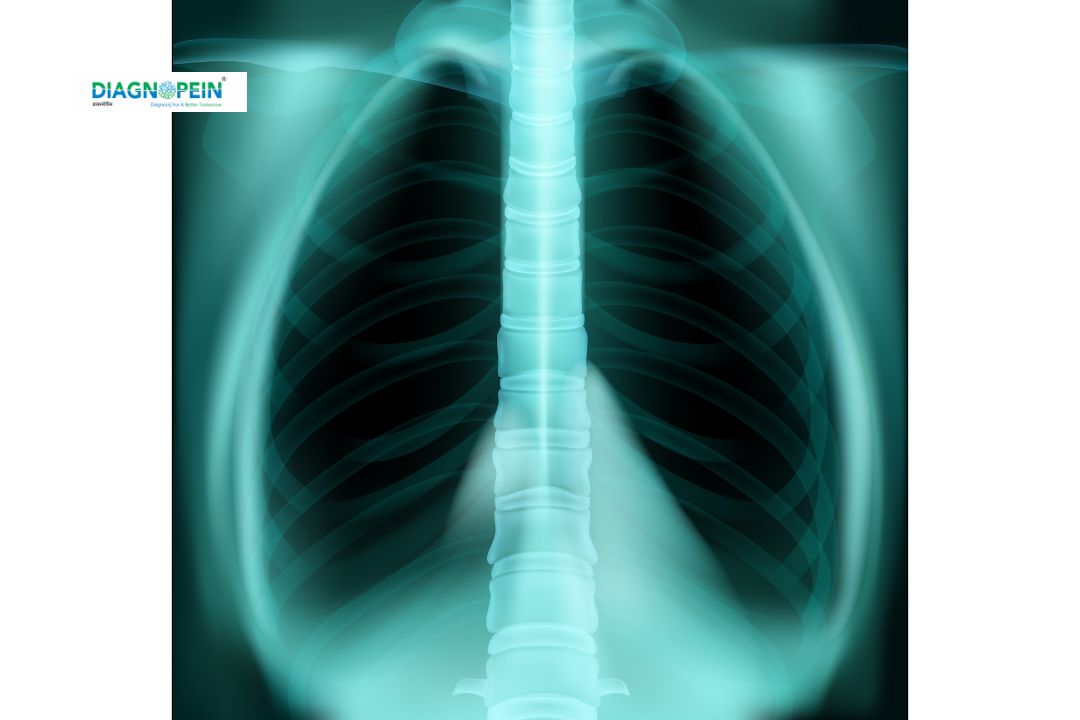

The X-Ray Thoracic AP/LAT is a diagnostic imaging test used to visualize the chest and thoracic region of the body. “AP” stands for Anteroposterior view (front to back) and “LAT” means Lateral view (side view). Together, these two perspectives help doctors assess the lungs, ribs, spine, and heart area in detail.

This test plays a crucial role in diagnosing respiratory problems, lung infections, fractures, and other thoracic abnormalities. It’s a quick, safe, and non-invasive imaging technique commonly recommended in clinical examinations and hospitals.